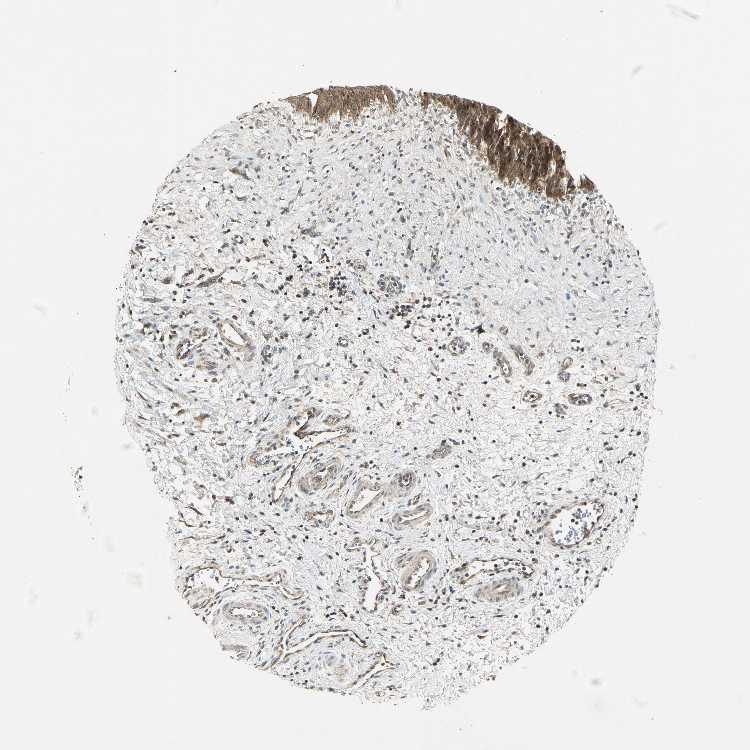

URINARY BLADDER - Antibody stainingi

Antibody staining in the annotated cell types in the current human tissue is reported as not detected, low, medium, or high, based on conventional immunohistochemistry profiling in selected tissues. This score is based on the combination of the staining intensity and fraction of stained cells.

Each image is clickable and will lead to virtual microscopy that enables deeper exploration of all samples and also displays staining intensity scores, fraction scores and subcellular localization as well as patient and tissue information for each sample.

Antibody HPA000903Antibody CAB006244

Urothelial cells MediumHigh